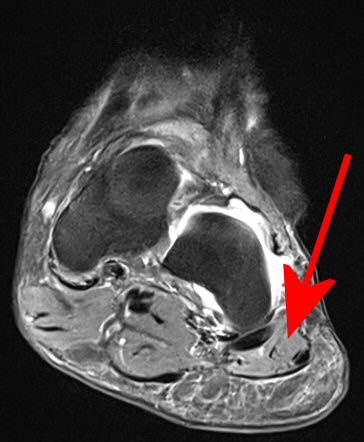

Klinisk diagnos, vid behov MR som visar atrofi av m. abduktor digiti minimi.

Abduktor digiti minimi, här normal, inte atrofierad